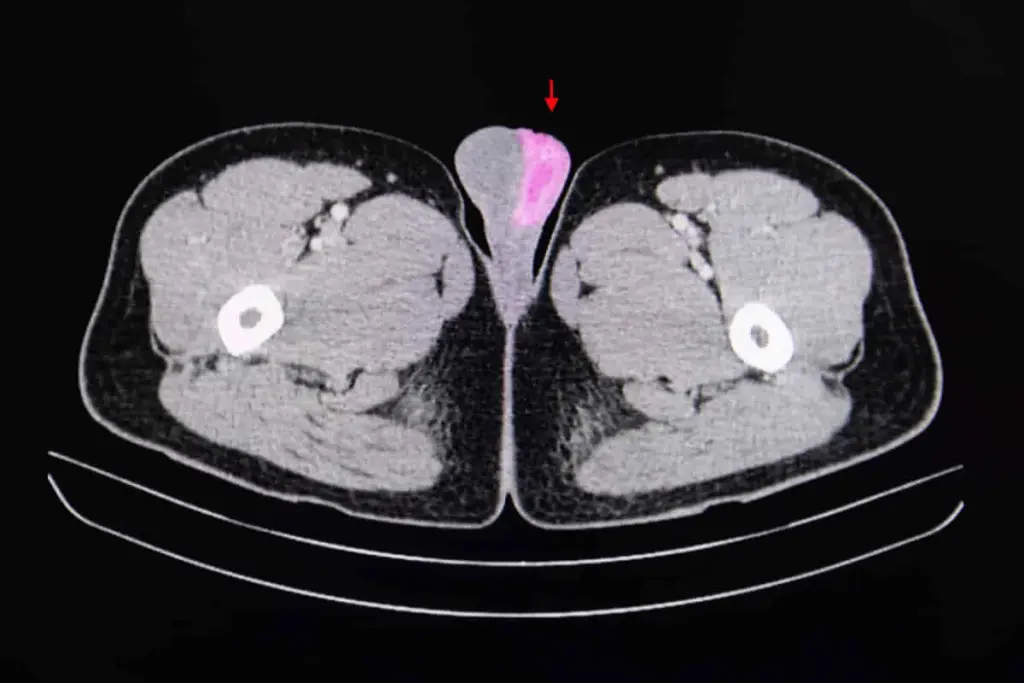

A precise cancer diagnosis is essential for creating an effective treatment plan. The process begins with a physical exam and a review of medical history. While imaging tests like CT scans, MRIs, and PET scans provide images of a tumor’s size and location, a biopsy is the definitive diagnostic tool. This involves removing a small tissue sample for a pathologist to examine. Blood tests may also be used to detect tumor markers. This collective data is then used to “stage” the cancer, a critical step that determines the extent of the disease.

When a symptom suggests cancer, a doctor will begin with a thorough physical exam and a review of medical history. If a specific area is suspected, the next step is typically an imaging test to visualize the inside of the body. However, cancer can only be confirmed with a biopsy. This procedure involves a specialist (such as a surgeon or radiologist) taking a sample of the suspicious tissue. A pathologist then analyzes these cells under a microscope to confirm the presence of cancer and identify its specific type.

We utilize state-of-the-art technology for both precise diagnosis and effective treatment. This includes high-resolution imaging (such as PET/CT and 3T MRI) for accurate staging, and advanced radiation therapy techniques (like IMRT/VMAT) that target tumors while sparing healthy tissue. Our access to genomic testing also enables the use of targeted therapies and immunotherapies, positioning us at the forefront of personalized medicine.